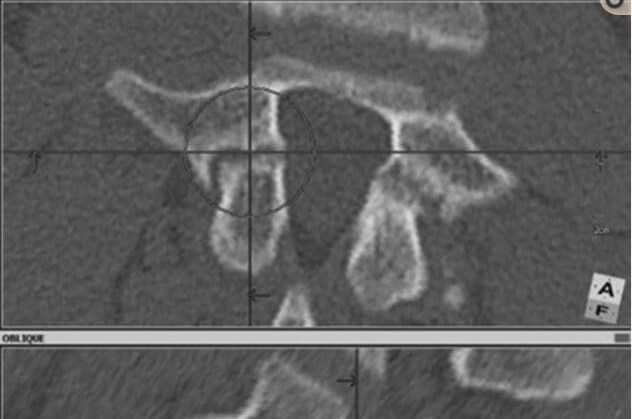

Wertebroplastyka polega na podaniu do uszkodzonego kręgu polimetakrylanu, czyli cementu kostnego stosowanego także do osadzania endoprotez. Substancja jest wprowadzana w postaci półpłynnej i po stężeniu tworzy w kręgu wewnętrzne rusztowanie, które wzmacnia kość i sprawia, że staje się twardsza od pozostałych.